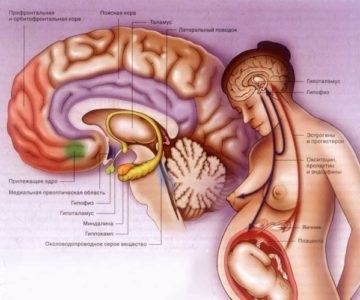

Ahol van. Nem található körülbelül a közepén a koponya alján az agy felületén. Ezen a ponton az alapja a koponyacsontok is egy speciális mélyedés, ez az úgynevezett török nyereg.

Szerkezetét. Különbséget tenni a két agyalapi. Elülső lebeny körülbelül hét tized teljes mérete az agyalapi mirigy. Ez van kialakítva nagy sűrűségű mirigyszövetekben. Töredék áthalad nagyszámú ereket. Itt van, hogy hormonokat termelnek.

Hátsó részesedése hipofízis szövetekben képződött, hasonló a tulajdonságait, hogy az idegrendszer. Nincs hormonok termelését. Hátulsó lebenye „működik” partner agyi idegi központja - a hipotalamuszban. Ez a rész az agy termel hormonokat oxitocin és a vazopresszin. majd elküldi őket a hátsó lebeny az agyalapi mirigy - a szó szoros értelmében a betét.

A legtöbb hipofízis hormonok - az úgynevezett trópusi. Ez azt jelenti, hogy a kémiai vegyületek jönnek más belső elválasztású mirigyek és szabályozzák működésüket. Az viszont vezérli az agyalapi mirigy befolyásolja a munkáját. stimulálják vagy gátolják annak aktivitását.